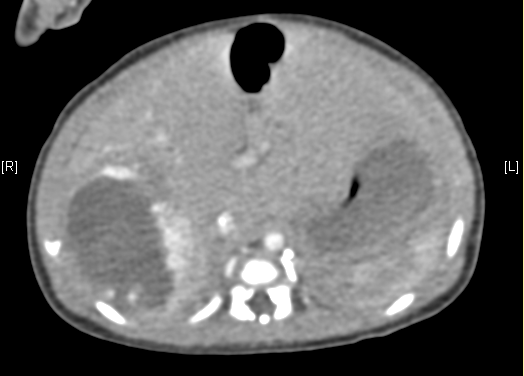

上腹部增强CT:肝脏右后叶血管源性肿瘤可能性大。上腹部增强CT:肝脏右后叶血管瘤可能性大。

术前CT检查:

动脉期

静脉期

平衡期